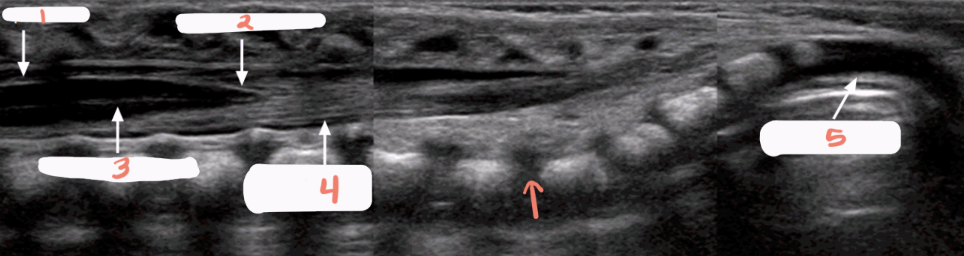

1

spinal cord

2

conus medullaris

3

central echo complex in hypoechoic spinal cord

4

filum terminale and nerve roots

5

unossified coccyx

arrow

lumbosacral joint

is this spine normal?

yes